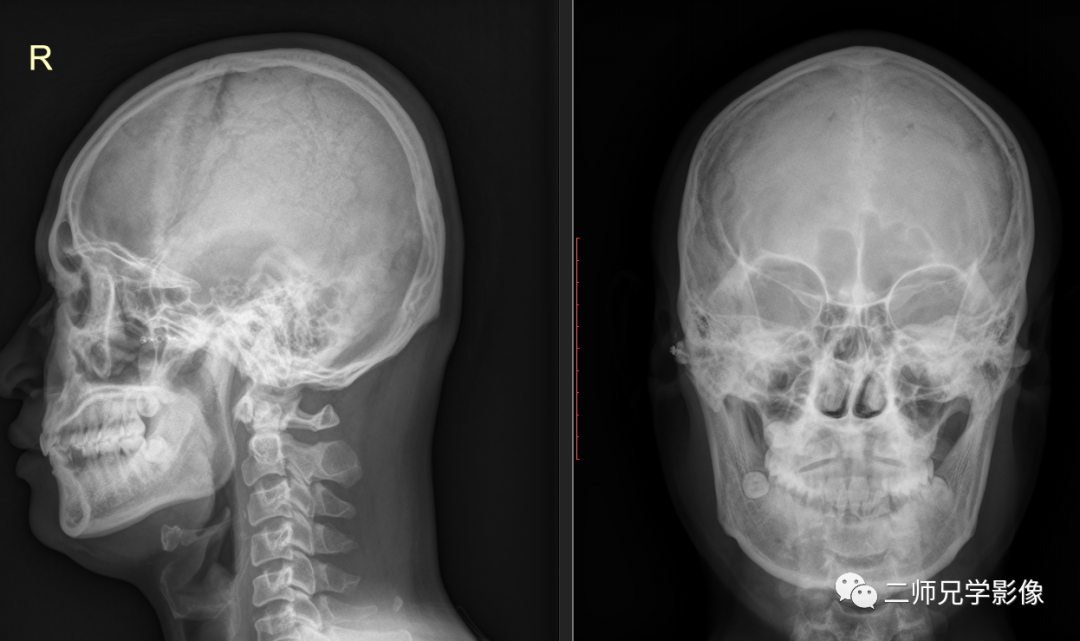

病例三:病人右颧骨骨折内固定复查,申请单:头颅正侧位

怎么取放射片放射拍片中的“几何学”,临床医生和技师都掌握了吗?_https://www.jmylbn.com_新闻资讯_第12张

右颧骨骨折内固定术后改变